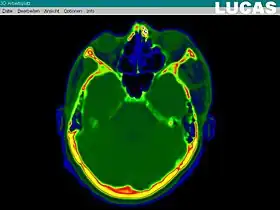

Image gathering ("segmentation") on the LUCAS workstation

The most important component for CAS is the development of an accurate model of the patient. This can be conducted through a number of medical imaging technologies including CT, MRI, x-rays, ultrasound plus many more. For the generation of this model, the anatomical region to be operated has to be scanned and uploaded into the computer system. It is possible to employ a number of scanning methods, with the datasets combined through data fusion techniques. The final objective is the creation of a 3D dataset that reproduces the exact geometrical situation of the normal and pathological tissues and structures of that region. Of the available scanning methods, the CT is preferred,[1] because MRI data sets are known to have volumetric deformations that may lead to inaccuracies. An example data set can include the collection of data compiled with 180 CT slices, that are 1 mm apart, each having 512 by 512 pixels. The contrasts of the 3D dataset (with its tens of millions of pixels) provide the detail of soft vs hard tissue structures, and thus allow a computer to differentiate, and visually separate for a human, the different tissues and structures. The image data taken from a patient will often include intentional landmark features, in order to be able to later realign the virtual dataset against the actual patient during surgery. See patient registration.

Image analysis involves the manipulation of the patients 3D model to extract relevant information from the data. Using the differing contrast levels of the different tissues within the imagery, as examples, a model can be changed to show just hard structures such as bone, or view the flow of arteries and veins through the brain.